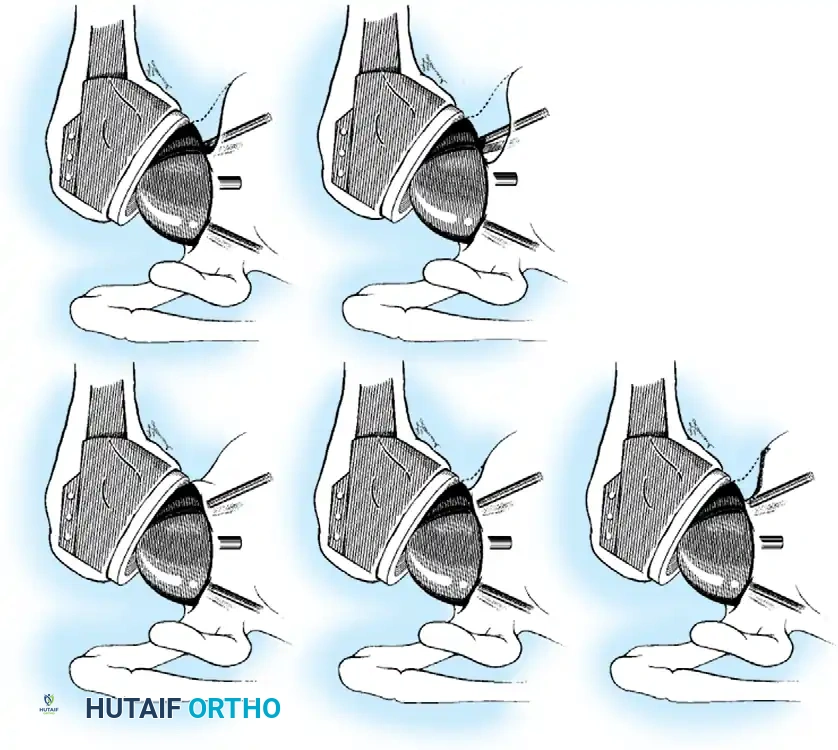

2. Subscapularis Management

The subscapularis is the gatekeeper to the joint. It can be managed via a tenotomy (1 cm medial to the lesser tuberosity), a lesser tuberosity osteotomy (LTO), or a subscapularis peel. LTO provides superior bone-to-bone healing and is increasingly favored.

3. Humeral Head Resection

Dislocate the humeral head anteriorly through external rotation and extension. Remove peripheral osteophytes to identify the true anatomical neck. The humeral cut is made along the anatomical neck, typically at 30 degrees of retroversion and 45 degrees of inclination.

Broach the humeral canal sequentially. Assess the trial components for stability, ensuring 50% posterior translation on the "drawer test" and no superior escape. Implant the final prosthesis (press-fit or cemented based on bone quality).

Securely repair the subscapularis using heavy non-absorbable sutures through transosseous tunnels.